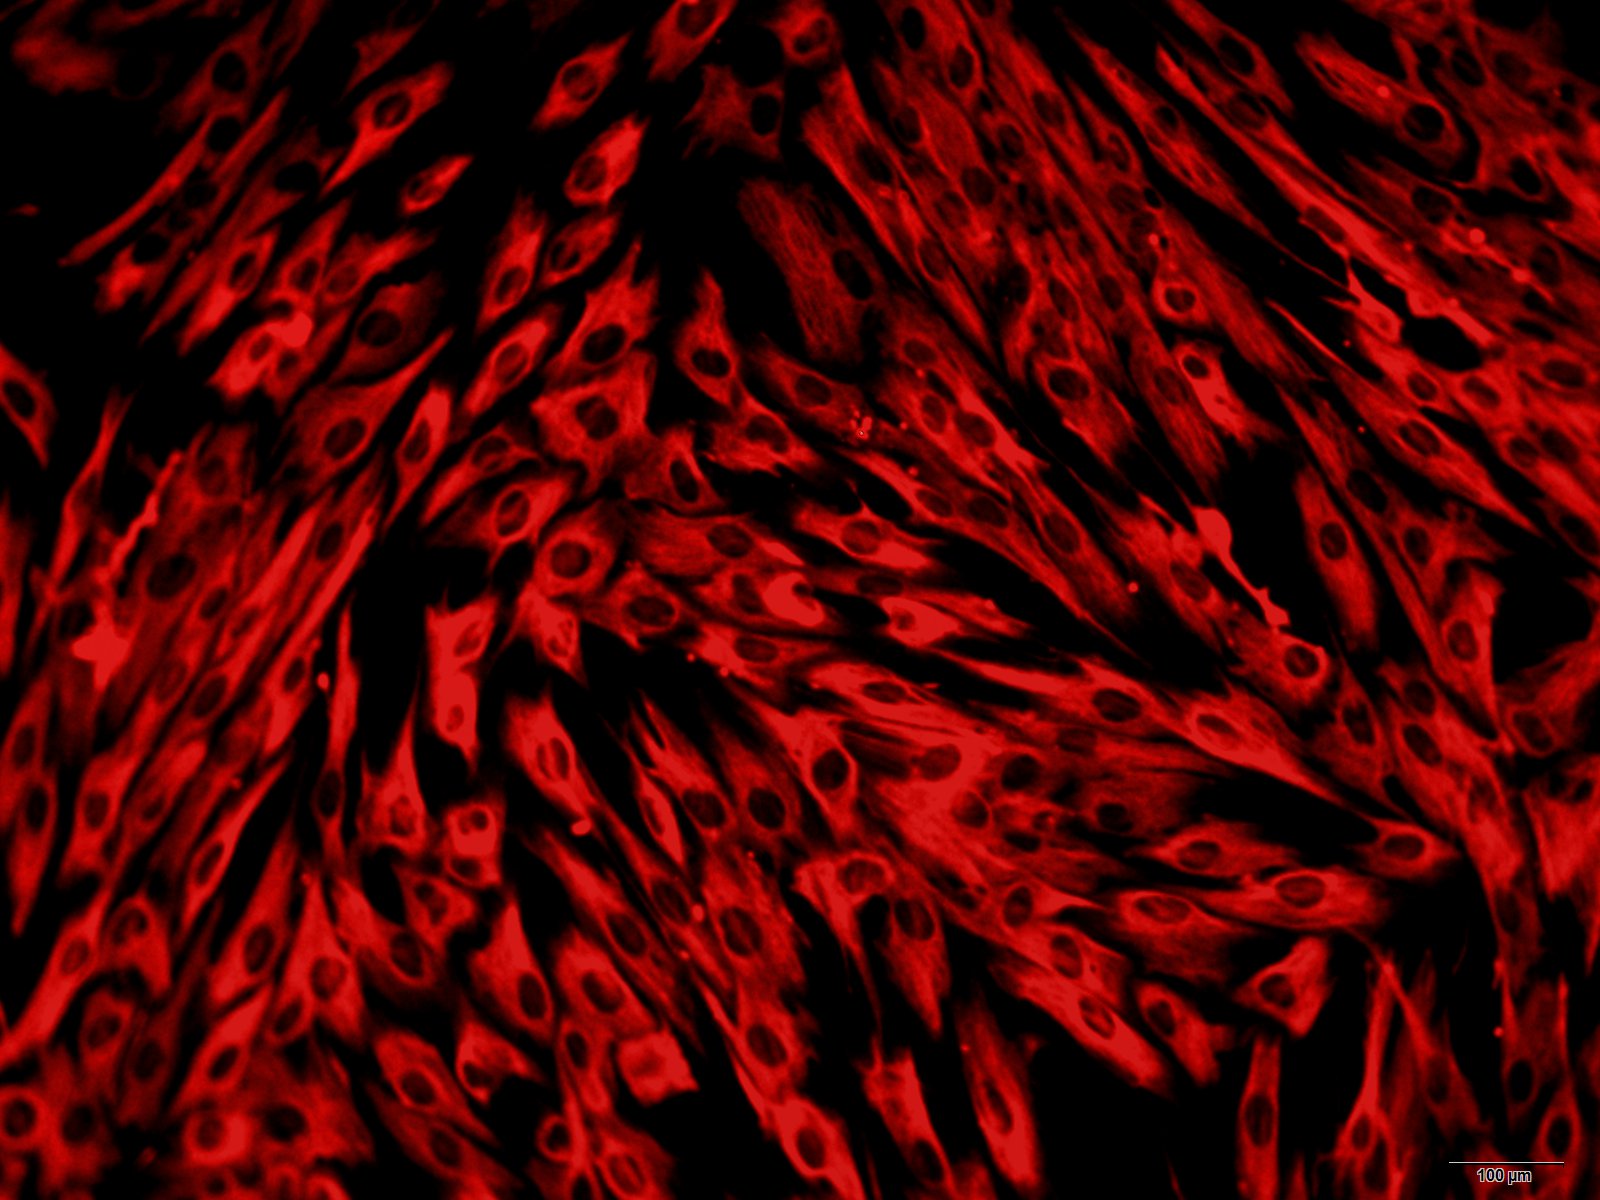

本公司生产的人脾淋巴细胞采用密度梯度离心法制备而来,细胞总量约为5×105/T25方瓶,细胞纯度可达90%以上,且不含有HIV-1、 HBV、HCV、支原体、细菌、酵母和真菌等。

文献和实验有间皮,被膜结缔组织伸入脾内形成许多分支的小梁,它们与门部分支形成的小梁相互连接构成一粗的支架。被膜和小梁内含有许多散在的平滑肌细胞,其收缩可调节脾内的血量,小梁之间的网状组织构成脾淋巴组织的微细支 架。 (2)白髓(white pulp):主要由淋巴细胞密集的淋巴组织构成,在新鲜脾的切面上呈分散的灰白色小点状,故称白髓。它又要分为动脉周围淋巴鞘和淋巴小结两部分。 动脉周围淋巴鞘(periarterial lymphatic sheath):是围绕在中央动脉(central

。脾小结中央有生发中心,主要是 B淋巴细胞和浆细胞。穿行于脾小结的动脉称中央动脉。呈筒状的白髓称淋巴鞘,包在中央动脉周围,其中有大量小淋巴细胞、巨噬细胞和一些浆细胞,紧靠中央动脉周围的主要是 T淋巴细胞。红髓分布在白髓之间,由脾索和脾窦构成,脾索除含淋巴细胞、巨噬细胞和浆细胞外,还含各类血细胞。脾窦即脾血窦,在脾索间穿行,窦腔宽 12~ 40微米。窦壁通透性大,脾索与脾窦内的细胞可穿过窦壁互相出入(脾索内的各类血细胞即来自脾窦)。窦壁内外贴附许多巨噬细胞。 脾的功能